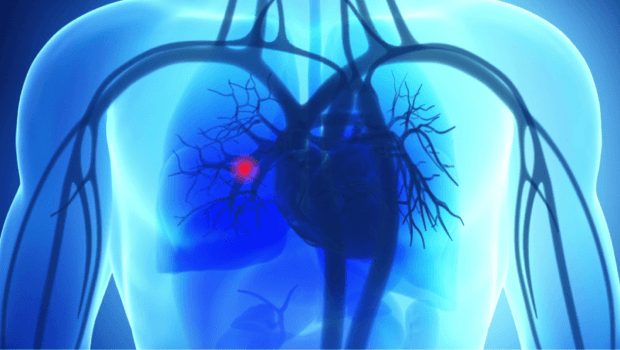

آمبولی یا لخته شدن خون در ریهها و سیستم گردش خون یکی از عوارض جدی پس از هر نوع جراحی است. بسیاری از بیماران نگران هستند که خطر آمبولی تا چه مدت پس از عمل وجود دارد و چگونه میتوان آن را شناسایی و پیشگیری کرد.

آمبولی زمانی رخ میدهد که لخته خون (ترومبوس) در رگها تشکیل شود و سپس به ریهها منتقل شود. این وضعیت میتواند تهدید کننده زندگی باشد و نیازمند تشخیص و درمان فوری است.